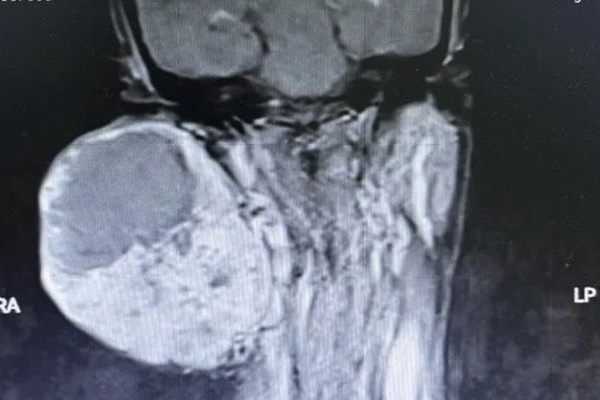

Kết quả chụp cộng hưởng từ cho thấy, khối u kích thước 10x15cm nằm sát nền sọ, dính bó mạch cảnh lên não trái, đẩy lệch đốt sống cổ, nên các bác sĩ phải tính toán kỹ trước mổ để giảm thiểu tối đa tác động lên các dây thần kinh, hạn chế các biến chứng sau mổ như nhắm mắt không kín, méo miệng.

Kết quả chụp cộng hưởng từ cho thấy, khối u có kích thước 10x15cm nằm sát nền sọ. (Ảnh: BVCC)